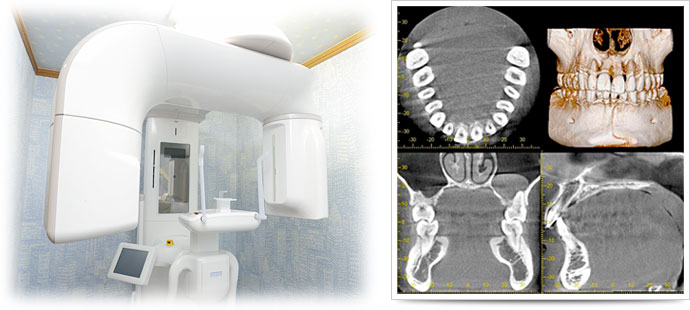

CTとは、従来の平面的(2次元)なレントゲン写真を立体的(3次元)に見ることができる装置で、骨の中に埋まっている歯の根の状態、曲がり具合、重要な神経や血管の位置などが正確に把握することができ、インプラントなどの外科処置や歯の神経・根っこの治療(根管治療)、歯周病の進行状態の確認などに非常に重要な機器です。歯科用CTでの撮影画像をもとに、的確な治療計画を立てることは、安心な治療への第一歩です。適切な治療方法を導くことは治療期間の短縮にもつながります。